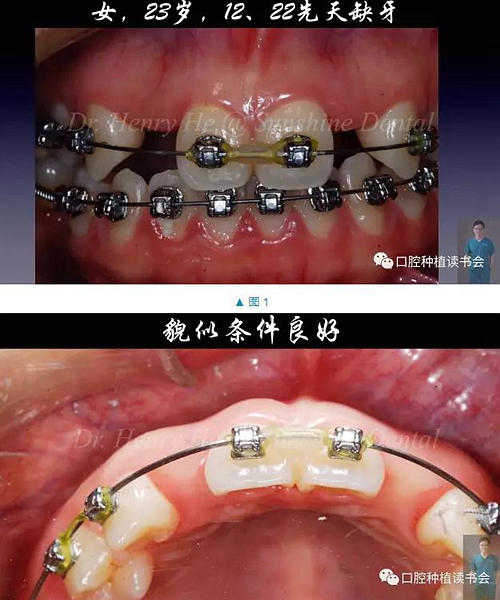

本臨床病例報告的患者為23歲的年輕女士,先天缺失12,22,為了給種植治療創(chuàng)造空間,2年前開始在外院正畸;正畸醫(yī)生認為修復空間調(diào)整到位后,告知患者可行種植治療。

口內(nèi)檢查發(fā)現(xiàn):患者口腔衛(wèi)生良好,牙周健康,除了12,22缺失外,未見其它問題。12,22缺隙近遠中大小約為8mm,臨床冠空間足夠(圖1,2)。患者中位笑線,中厚齦生物型,美觀要求很高(圖3)